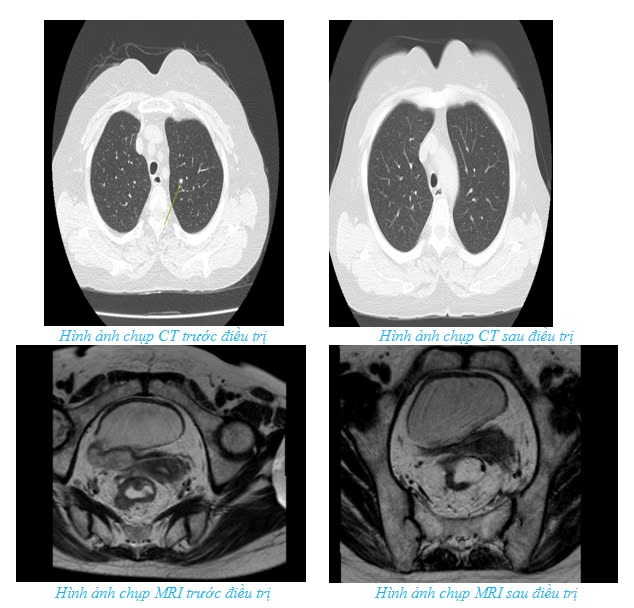

Một ví dụ nổi bật là bệnh nhân 62 tuổi được chẩn đoán ung thư trực tràng giai đoạn IV với di căn phổi. Trước đây, bệnh nhân này có thể chỉ được điều trị triệu chứng hoặc hóa trị toàn thân với tiên lượng dè dặt. Tuy nhiên, sau khi được hội chẩn tại Hội đồng ung thư, các bác sĩ quyết định sử dụng phác đồ TNT (total neoadjuvant therapy), nhằm thu nhỏ khối u và kiểm soát di căn. Sau 4 tháng điều trị, bệnh nhân có sự cải thiện rõ rệt với khối u tại trực tràng thu nhỏ và không còn di căn phổi.

Bệnh nhân tiếp tục được điều trị hóa xạ trị tiền phẫu và tiến hành phẫu thuật triệt căn. Sau khi điều trị, bệnh nhân có thể quay trở lại sinh hoạt bình thường.